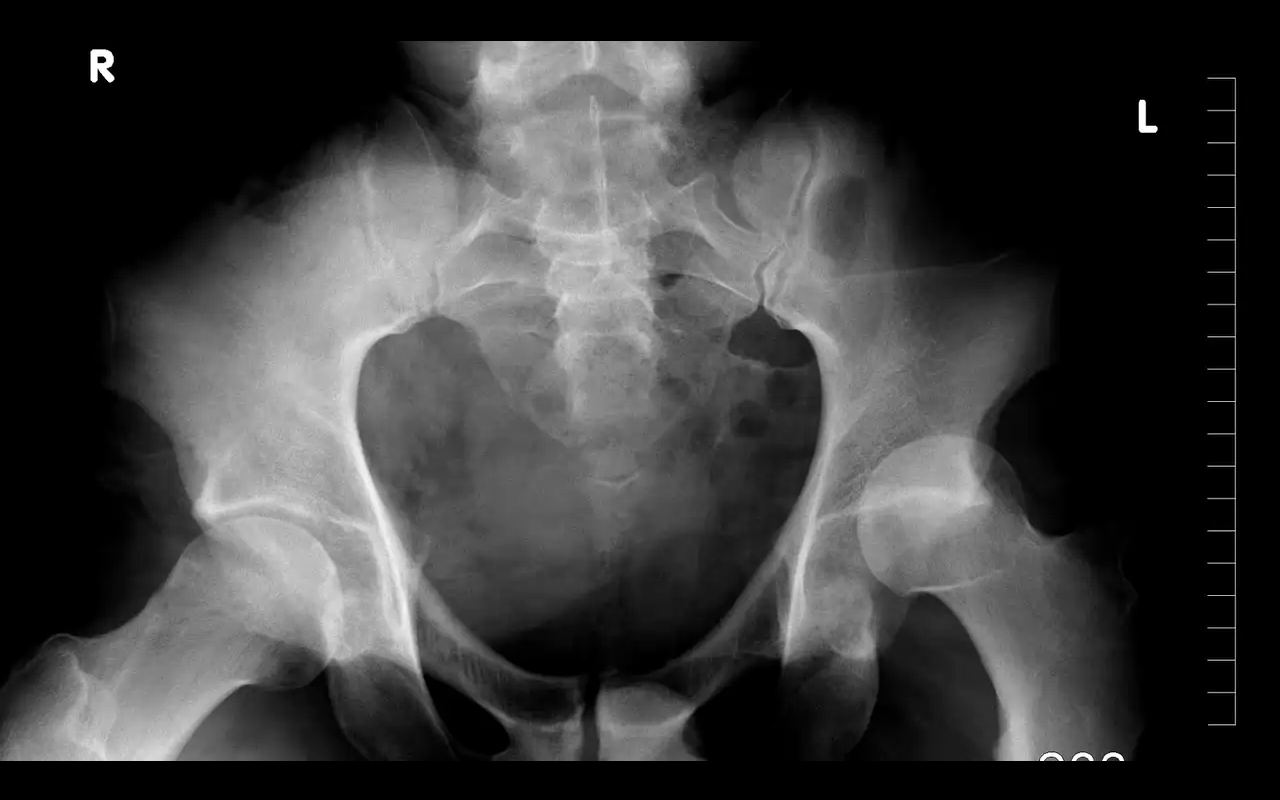

Die Saison 2013 war die bisweilen herausforderndste überhaupt für Dane Tudor. Nachdem der Scott Rider sich im Januar die Hüfte auskugelte, was nebenbei gesagt eine...